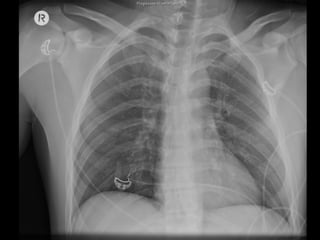

A Maintaining

B Sats 99% on 15L Oxygen

• R pneumocath

C sBP 80, HR 130

• 2 x 18G

D GCS 14

E Massive truncal abrasions/degloving

Large scalp wound

Resus

Intubation

Bilateral ICC’s

Right Lower Limb splint

Scalp wound closure

IDC insertion – frank blood

6 x PRBCs, 2 x FFP, 1 x Plat

– Transient responder, ++ blood dependent

– sBP 90 ! 120 ! 70

– R Subclavian MAC line

! To CT